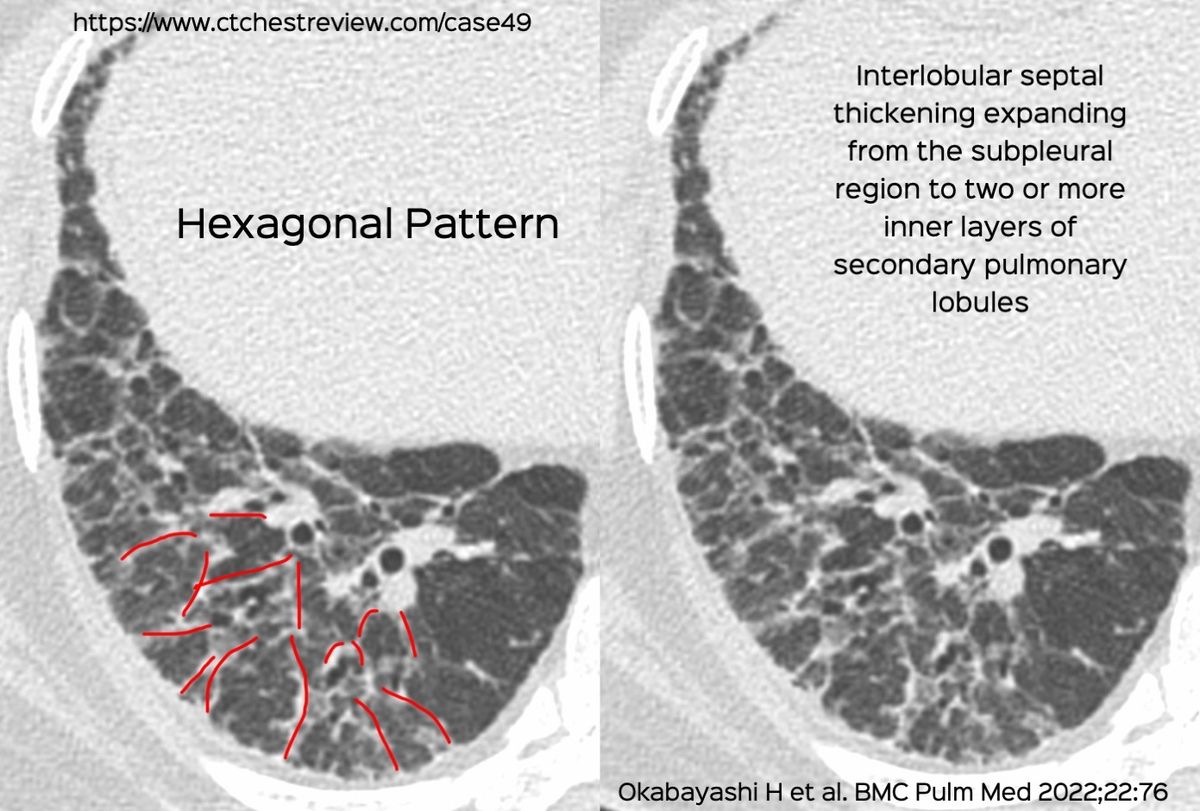

70-years old with a fibrosing ILD that shows a usual interstitial pneumonia (UIP) - like pattern on the left, but a three-density sign on the right suggesting this could be a bronchiolocentric interstitial pneumonia (BIP) pattern, suggestive of fibrotic hypersensitivity pneumonitis, if there is no underlying etiology (Fig. 1).